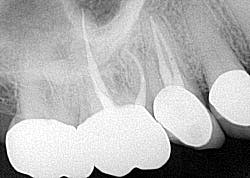

A 72-year-old male presented for a comprehensive exam with a chief complaint that the tooth on the upper right side had had a root canal done twice, but he was still in pain. He was wondering if there was a possible sinus infection. Health history included a pacemaker, Warfarin, and thyroid cancer.

Testing of the upper right side was, for the most part, inconclusive, aside from some 6 mm pockets in the upper right quadrant. Radiograph was WNL (figure 11). A potential sinus infection was discussed, along with the possibility of a periodontal abscess. The patient was placed on antibiotics, referred to an ENT, and had scaling and root planing done on the upper right quadrant.

The report from the ENT was negative. The symptoms persisted and, in fact, started to worsen. The likelihood of a vertical root fracture was then discussed with the patient. He was referred to an endodontist who took a CBCT scan.

Evaluation by the endodontist showed a very small direct, vertical 9 mm drop on the lingual with radiolucency on the lingual root in the scan about halfway down (figure 12). Given the history of the double root canal, symptoms, and radiographic evidence, it was concluded that the patient had sustained a vertical root fracture on the lingual root of tooth No. 4. Prognosis was poor, and the tooth was removed with discussion regarding replacement options.

This case is a classic example of how elusive diagnosing these types of teeth can be and how critical a comprehensive assessment is to produce the most accurate diagnosis.

Editor’s note: The CBCT scan in case No. 2 (figure 12) is courtesy of Joseph A. Petrino, DDS, MS; Missoula, Montana.